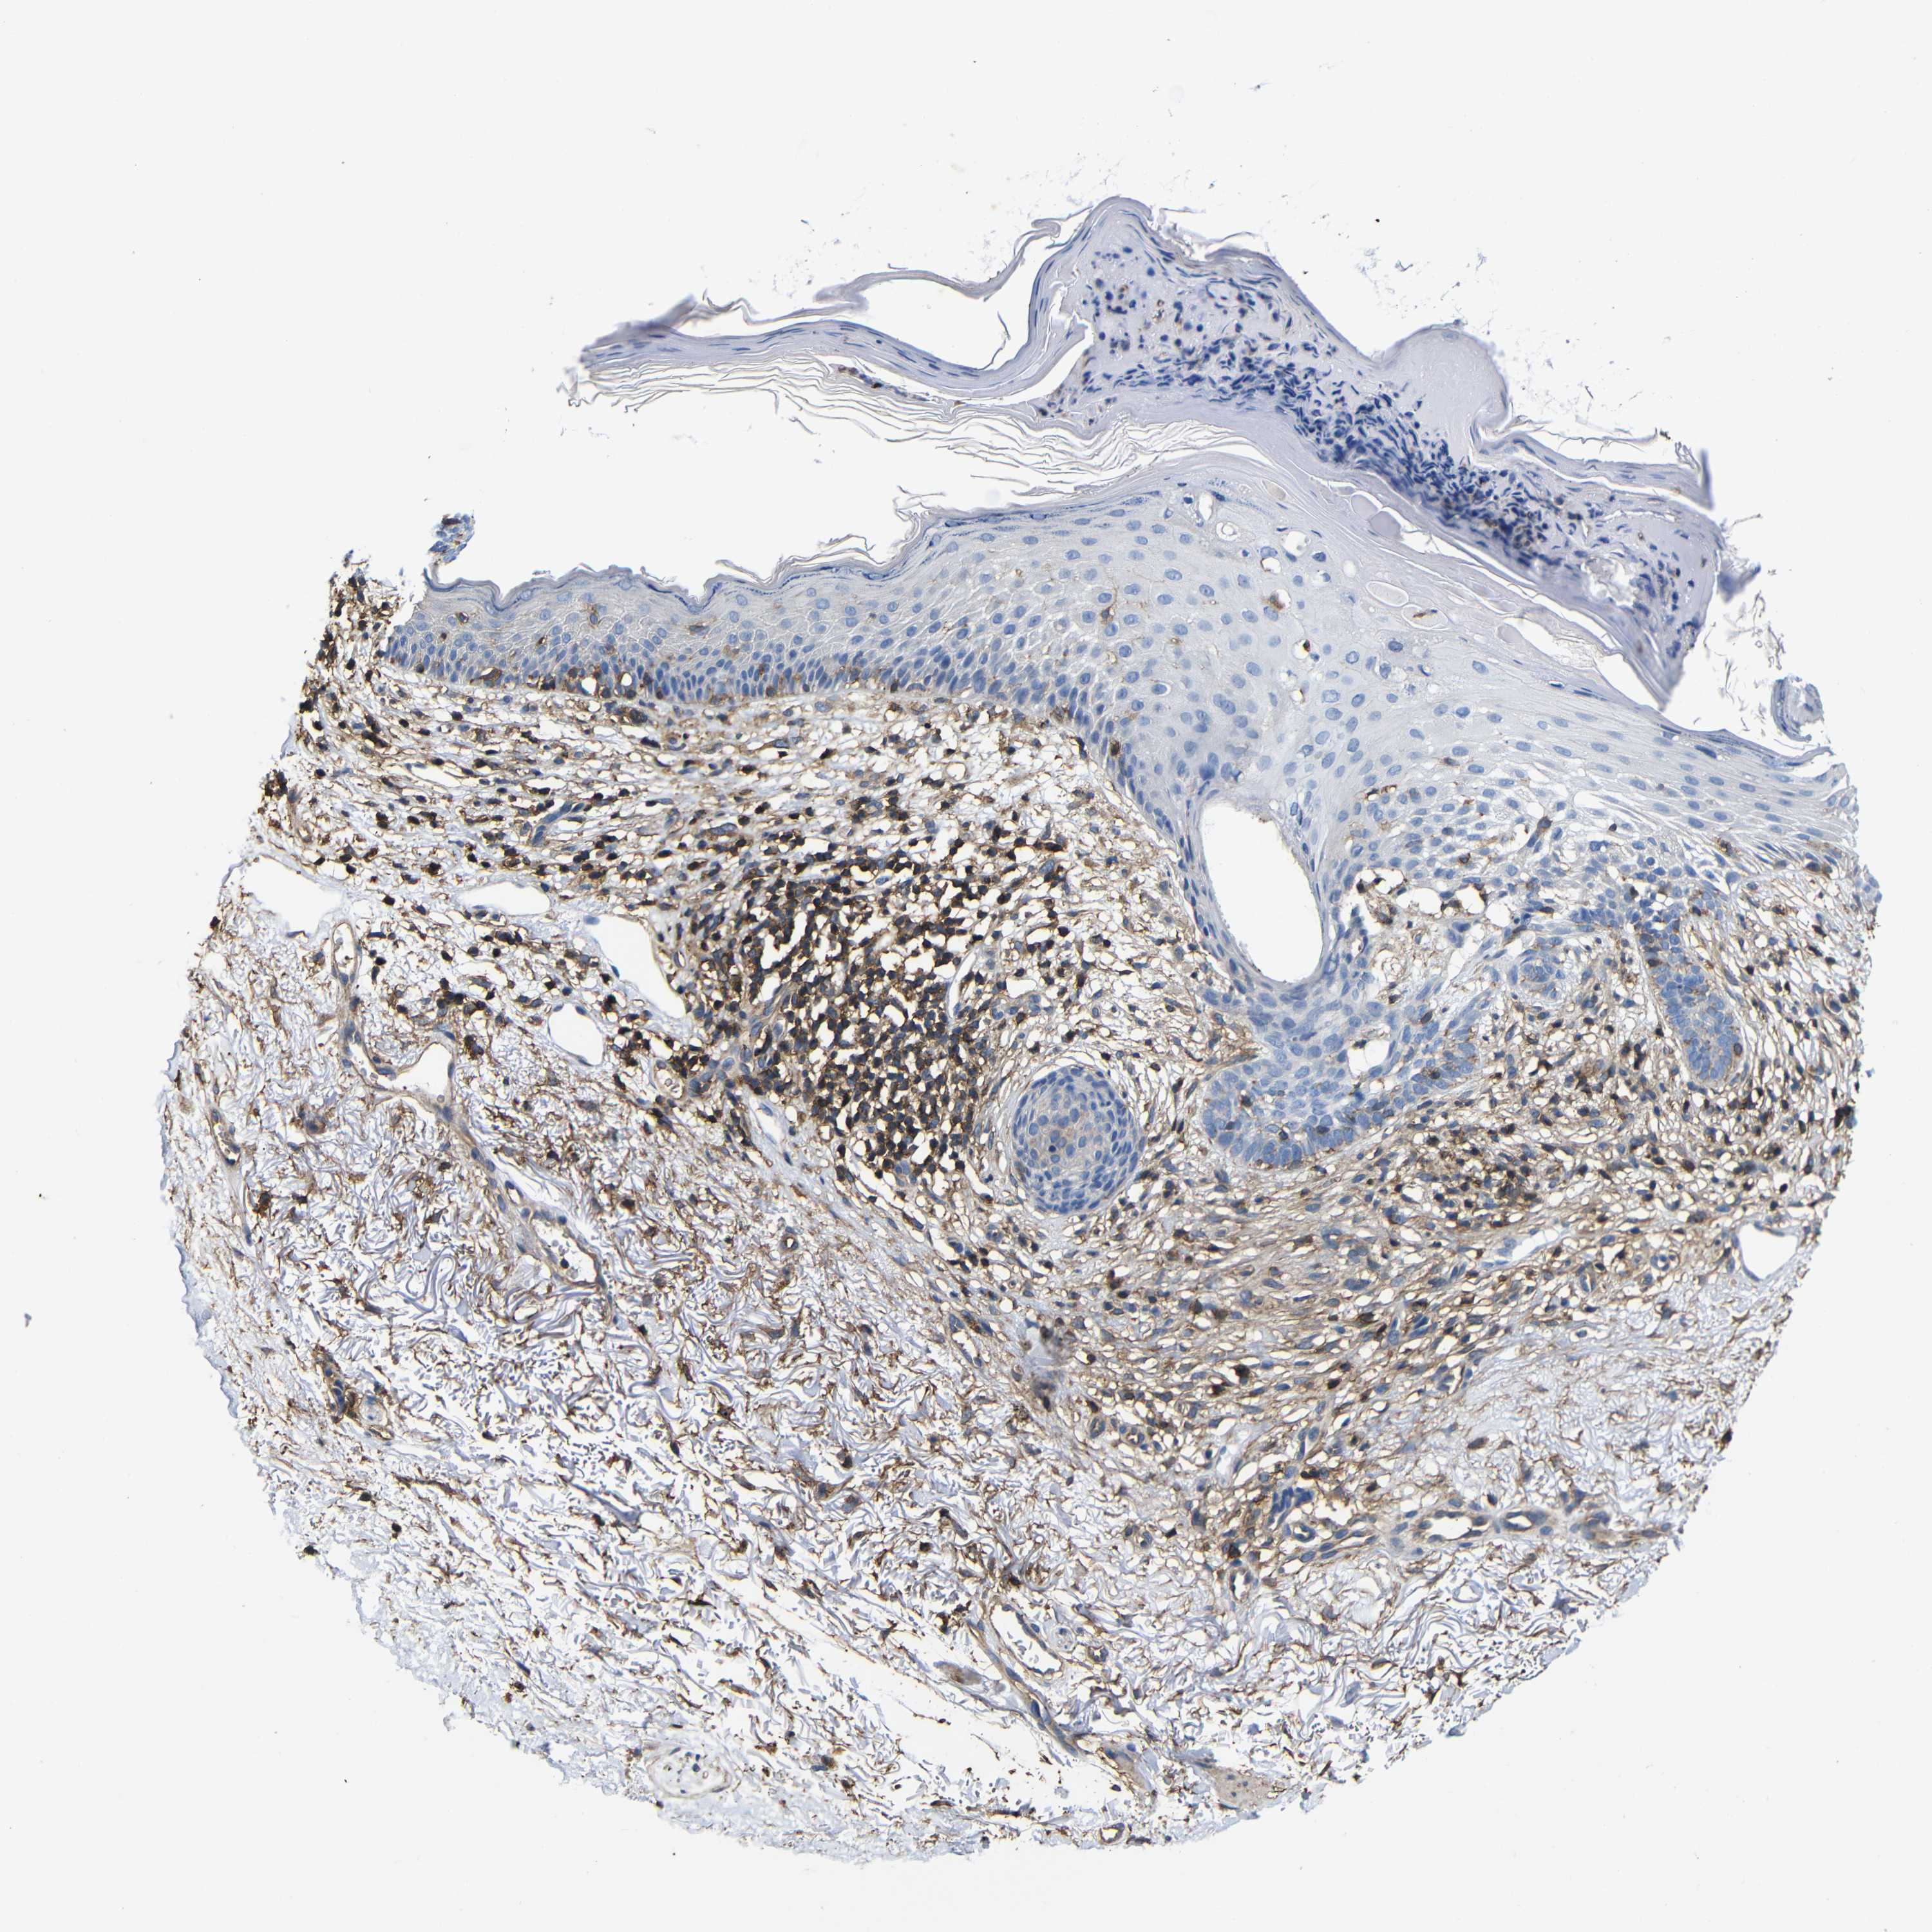

SKIN CANCER - Protein expressioni

A mouse-over function shows sample information and annotation data. Click on an image to view it in a full screen mode. Samples can be filtered based on level of antibody staining by selecting one or several of the following categories: high, medium, low and not detected. The assay and annotation is described here.

Each image is clickable and will lead to virtual microscopy that enables deeper exploration of all samples and also displays staining intensity scores, fraction scores and subcellular localization as well as patient and tissue information for each sample.

Antibody CAB009092

Staining

Moderate

75%-25%

Cytoplasmic/membranous

Basal cell carcinoma